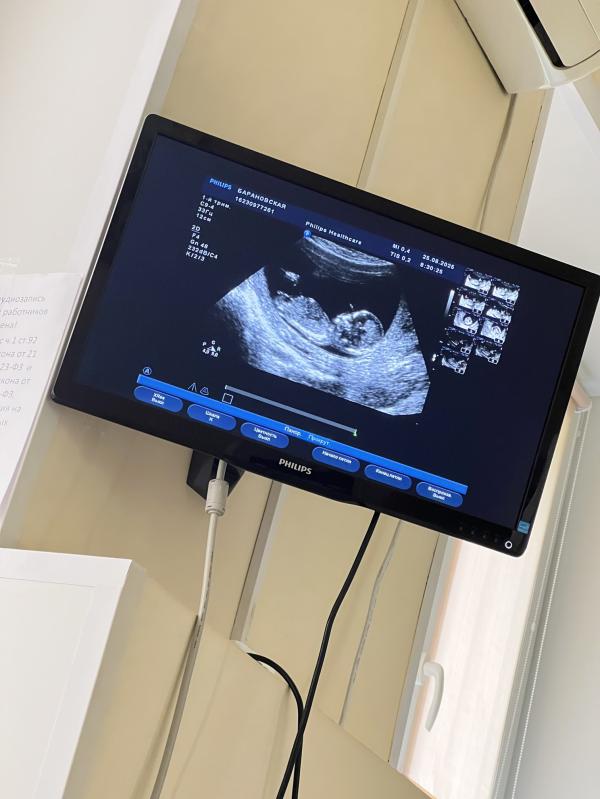

Скрининг пройден) малышусик соответствует сроку 13.4, все сходится 🥰 пдр поставили 28.02-01.03.2026. Живота до сих пор нет) на работе пока еще не сообщила.